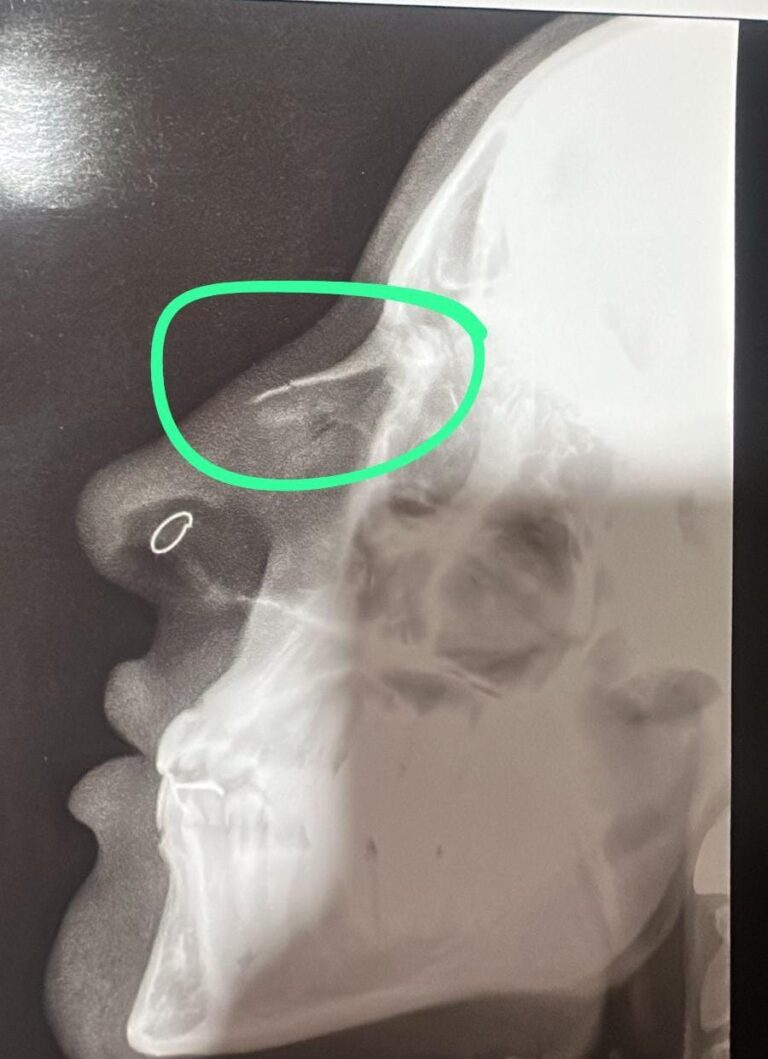

Após a agressão, a mulher procurou atendimento médico em um pronto-socorro particular na região central da cidade e, posteriormente, compareceu ao plantão policial, onde formalizou a denúncia. Uma cópia da radiografia, que aponta fratura, foi anexada à queixa.